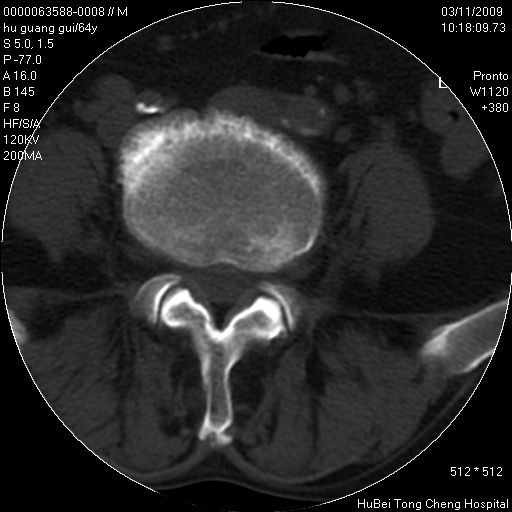

患者 男,64岁。腰痛十余天。(临床未提供其他病史)

临床诊断:腰痛原因待查(腰椎间盘突出症?)。

腰椎间盘ct轴位平扫(层厚5mm,层距4mm),图像如下:

腰椎退行性变,腰4—5椎间盘膨出。

右侧骶骨侧块骨侵蚀,骶髂关节骨性关节面破坏,并见软组织肿块,考虑骨转移瘤可能,进一步检查。

1.腰椎退行性变,腰4—5椎间盘膨出。

2.右侧骶骨侧块骨侵蚀,骶髂关节骨性关节面破坏,并见软组织肿块,考虑:脊索瘤,骨转移瘤可能,进一步检查。

1)腰椎退行性变,l4—5椎间盘膨出。2)骶骨右侧块骨转移瘤可能,3)水平骶椎。建议作一步检查。